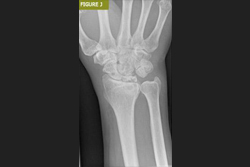

Daha önce de belirtildiği gibi, hasarlı veya tahrip olmuş eklemlerde eklem artroplastisi endikedir. Bu dejenerasyona bağlı olabileceği gibi daha önceki bir yaralanmanın sonucu da olabilir (Şekil A ve B). Romatoid artrit ve gut gibi inflamatuar artritlerin artan prevalansı ve birçok kişi tarafından benimsenen varlıklı yaşam tarzları ile eklem kıkırdağı dejenerasyonunun bir sonucu olarak ağrılı, şişmiş eklemler yaygın bir olaydır. Bu durumlarda eklem artroplastisi ağrıyı azalttığı ve hareket aralığını iyileştirdiği veya en azından koruduğu için faydalı olacaktır.

El eklemi değiştirme cerrahisi, el eklemlerinde ciddi hasar olan hastalar için uygulanan bir cerrahi yöntemdir. Bu işlem, özellikle el eklemi değiştirme ve bilek ve parmak eklem değişimi gibi durumlarda tercih edilir.

Cerrahi süreç, hasarlı eklem yüzeylerinin çıkarılarak yerine protezlerin yerleştirilmesini içerir.

Bilek artroplastisi, bilek eklemlerinde ciddi hasar olan hastalar için uygulanan bir cerrahi yöntemdir. Bu işlem, özellikle bilek değiştirme ameliyatı olarak da bilinir ve hastaların ağrılarını azaltırken aynı zamanda eklem hareketliliğini de artırır.